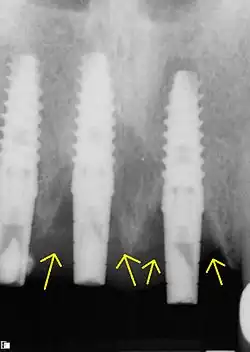

Die Diagnostik der Periimplantitis erfolgt in zwei Schritten. Zunächst erfolgt die klinische Diagnostik durch Sondierung des periimplantären Bereichs mittels Parodontalsonden. Eine auftretende Blutung, die auch von einer Eiterentleerung begleitet sein kann, führt zur Verdachtsdiagnose der Periimplantitis, die anschließend mittels Röntgenaufnahmen, bevorzugt durch intraorale Zahnfilmaufnahmen, von einer reinen Mukositis differentialdiagnostisch abgegrenzt beziehungsweise bestätigt werden kann. Die Mukositis verläuft suprakrestal, also oberhalb des Knochensaums. Die Defektklassifizierung erfolgt nach Schwarz et al.[6]